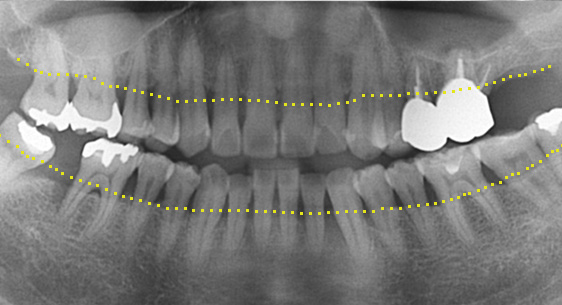

기존 신경치료는 양호한 상태이나 치근부위에

염증과 치조골 소실이 진행 중

치아 뿌리 쪽 잇몸을 절개하고 치조골 부위의

염증조직을 제거. (난이도 중)